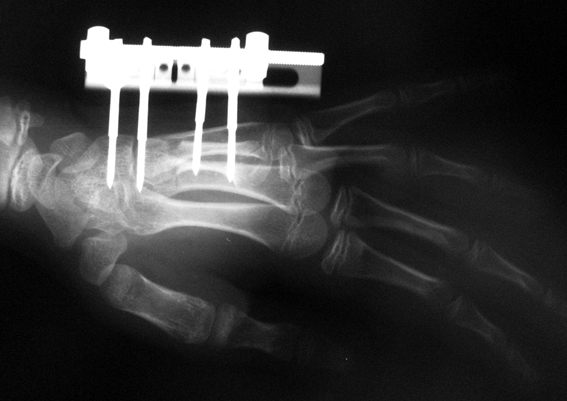

Doğuştan metakarp ve metatars kısalıklarının redavisi için pek çok teknik tanımlanmakla birlikte en çok akut uzatma sonrası kemik uçlarına greft konması ve distraksiyon osteogenezi (kallotasis) kullanılmaktadır. 1 cm.den daha fazla uzatma gereken olgularda kallotasis yöntemi önerilmektedir. Kliniğimizde de metatars ve metakarp uzatma için unilateral eksternal fiksatör ve sirküler eksternal fiksatör yardımıyla distraksiyon osteogenezi yöntemi tercih edilmektedir.